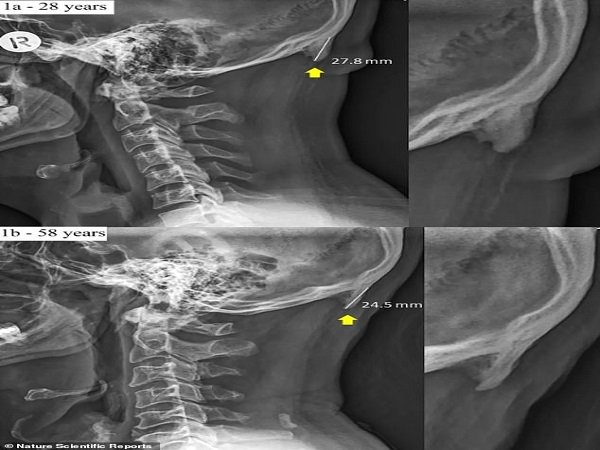

அதிகமா செல்போன்ல பேசினாதால தலையில கொம்பு முளைத்த விபரீதம்... நீங்களே பாருங்களேன்...

அதிக அளவு மொபைல் போன் பயன்படுத்துகிற இளம் வயதினருக்கு தலையில் கொம்பு முளைக்கிறதாம். என்ன ஆச்சர்யமாக இருக்கிறதா? கதை விடுகிறோம் என்று தோன்றுகிறதா? இல்லவே இல்லை. நிஜமாகவே தான். தொடர்ந்து படித்து முழுவதை

இன்றைய நாட்களில் மொபைல் போன் அதிகம் பயன்படுத்தும் இளம் வயதினருக்கு தலையின் பின்புறம் கொம்பு முளைக்கிறது. குறிப்பாக ஸ்மார்ட்போன், டேப்லெட் போன்றவற்றைப் பயன்படுத்தும் நபர்களுக்கு இந்த பாதிப்பு ஏற்படுகிறது. இவர்கள் தலையில் கூர்முனைகள் கொண்ட எலும்பு ஒன்று வளர்வதாக உண்மையில் விஞ்ஞானிகள் தெரிவிக்கின்றனர். இது முற்றிலும் உண்மை.

தற்போது சில காலங்களாக சில நபர்களுக்கு தலையின் பின்புறம் பிடரியில் ஒரு அசாதாரண புடைப்பு ஏற்படுவதாக ஆறாய்ச்சியாளர்கள் கூறுகின்றனர். இதனை ஆங்கிலத்தில் enlarged external occipital protuberances என்று கூறுகின்றனர். இது மண்டையோட்டின் அடிப்பகுதியில் காணப்படுகிறது.

ஆரம்ப காலத்தில் இந்த நிலை மிகவும் அரிதாக இருந்து வந்தது. ஆனால் தற்போது, நமது விரல்கள் கொண்டு தொடும்போது அடையாளம் காணக்கூடிய அளவிற்கு இவை தெளிவாக தெரிகிறது. குறிப்பாக முடி இல்லாத வழுக்கைத் தலையில் இவை தெளிவாக காணக்கூடியதாக உள்ளன.

இந்த வகை எலும்பு இளம் வயதினருக்கு மிக விரைவாக வளருவதாக இந்த நிலை பற்றி மேலும் அறியப்படுகிறது. இந்த ஆராய்ச்சியின் ஆய்வறிக்கையில், 18-30 வயது உள்ள இளம் வயதினருக்கு இந்த கட்டி பரவலாக காணப்படுவதாக கூறப்படுகிறது. ஆஸ்திரேலியாவில் உள்ள குயின்ஸ்லாந்தின் சன்ஷைன் கோஸ்ட் பல்கலைக் கழகத்தில் இந்த ஆராய்ச்சி நடைபெற்றது.

இந்த கண்டுபிடிப்பை உறுதி செய்வதற்கு, 18-86 வயது வரை உள்ள நபர்களை தேர்வு செய்து, அவர்களின் மண்டை ஓடு ஸ்கேன் செய்யப்பட்டது. கடந்த பத்து ஆண்டுகளில் மிக அதிக நபர்களுக்கு இந்த எலும்பு புடைப்பு காணப்படுவதாக அறியப்பட்டுள்ளது.

இன்றைய நாட்களில் இந்த பாதிப்பு அதிகம் காணப்படுவதற்கு காரணம் , மக்கள் கீழே குனிந்து பார்ப்பதில் அதிக நேரத்தை செலவிடுவது தான் என்று மருத்துவர்கள் பரிந்துரைக்கின்றனர். நீண்ட நேரம் ஸ்மார்ட்போன், லேப்டாப், டேப்லெட் போன்றவற்றை குனிந்தபடி பார்த்துக் கொண்டே இருப்பதால், அதிகம் பயன்படுத்தப்படாத இந்த பகுதி அதிக சிரமத்தை ஏற்றுக் கொள்கிறது. இதனால் இந்த பகுதிகளில் சில மாற்றங்கள் ஏற்படுகின்றன.

மண்டை ஓட்டை நேராக நிறுத்தி வைப்பதற்காக முயற்சித்து, கழுத்தையும் தலையின் பின் பகுதியையும் இணைக்கும் தசைகள் அதிகம் பயன்படுத்தப்படுவதால் இந்த தசைகள் பெரிதாகவும் வலிமையாகவும் மாறுகின்றன. இதனால் உடற் கூட்டில் ஒரு புதிய அடுக்கு எலும்பு வளர வழிவகுத்து, இந்த பகுதியை வலுப்படுத்தவும் விரிவாக்கவும் உதவுகிறது.

தற்போதைய நாட்களில் இந்த எலும்பு புடைப்பின் அளவு சராசரியாக 2.6 செமி (1 இன்ச்) இருப்பதாகவும் இந்த அளவு 1996ம் ஆண்டு எடுக்கப்பட்ட அளவை விட பெரிதாக இருப்பதாகவும் கூறப்படுகிறது.